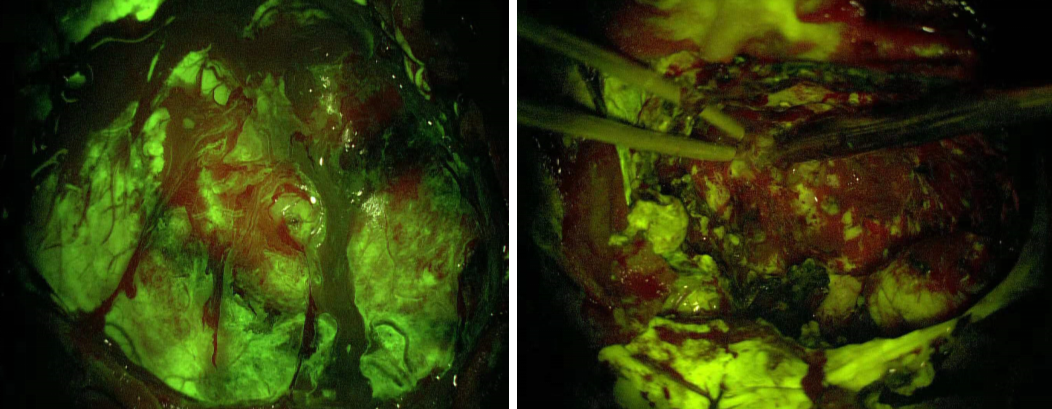

术后头颅CT